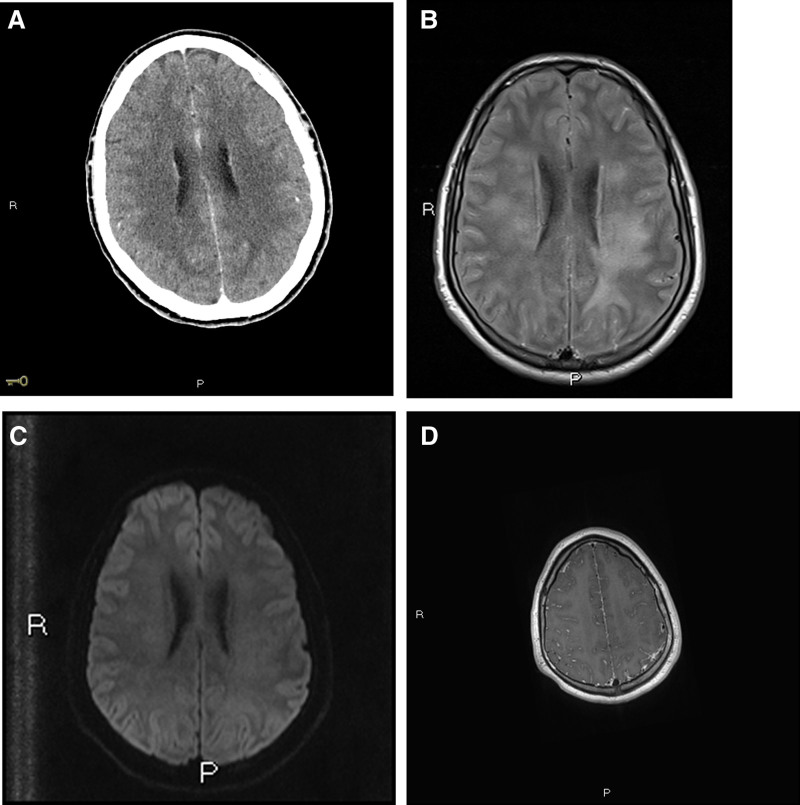

Background: Mpox, formerly known as monkeypox, is an infectious disease caused by the mpox virus. Systemic involvement is rare and mpox-associated meningoencephalitis is an uncommon clinical presentation. Because mpox-associated meningoencephalitis is characterized by nonspecific clinical and incidental imaging findings, the disease is difficult to diagnose.

Case summary: We present a case of fatal mpox-associated meningoencephalitis with negative polymerase chain reaction in cerebrospinal fluid (CSF) diagnosed at autopsy. A young immunocompetent patient with no significant medical history initially presented with genital mpox infection. Within 48 hours, he showed neurologic involvement requiring orotracheal intubation. His condition deteriorated rapidly, progressing to cerebral edema and brain death consistent with meningoencephalitis. Despite negative testing for mpox virus in CSF, the diagnosis was confirmed posthumously by autopsy, where histological examination revealed the presence of mpox virus in brain tissue.

Conclusions: Mpox-associated meningoencephalitis should be considered as a potential diagnosis even in the absence of the mpox virus genome in CSF.